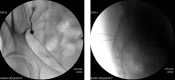

Figure 24.. A, B, C and D: Spinal Cord stimulator Lead Placement for Low Back Pain as Well as Radicular Pain in a Post-Laminectomy Pain Patient Using a Dual Lead Configuration

The lesion is generated between the tips of the probes and provides a near complete coverage of the posterior annulus.